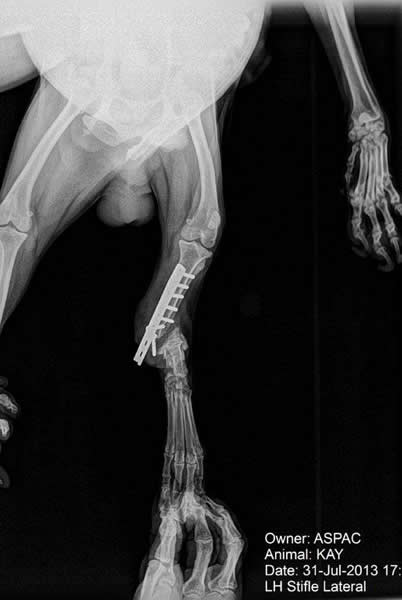

KAY

Kay fue recogido en Ribera de Cabanes. Tenía una antigua cirugía en su pata trasera

izquierda. La prótesis se rompió y Kay vivía en la calle con un agujero en su pata por donde se

salía la prótesis. El dueño era consciente de su estado y permitía que viviera en estas

condiciones. Tras ser rescatado por ASPAC, Kay fue tratado contra la Leishmania y fue intervenido quirúrgicamente

para frenar la infección de su pata.

Tras retirársele los hierros de la operación, Kay será operado de nuevo

para reconstruir su pata.